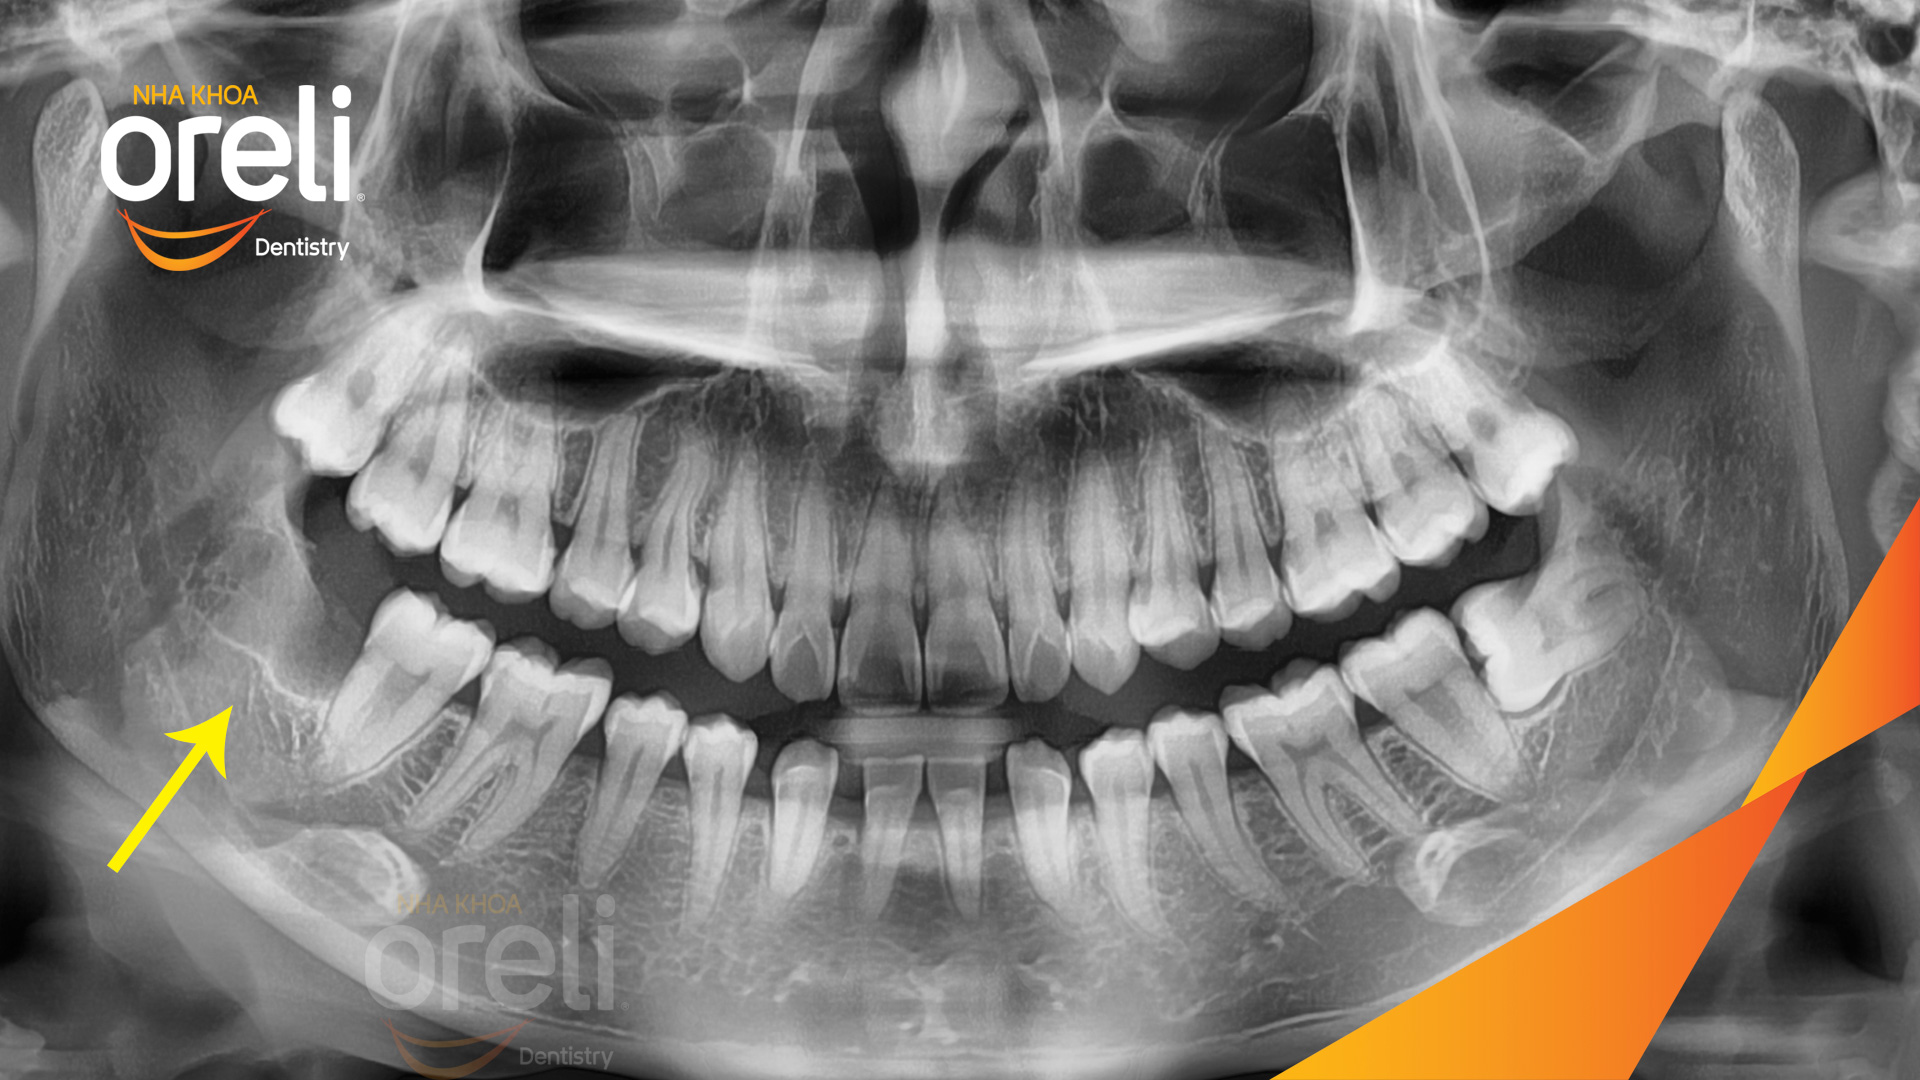

Nhổ răng khôn hàm dưới – Case tại Oreli Buôn Ma Thuột

Nhổ răng khôn

Mọc lệch

Xem thêm